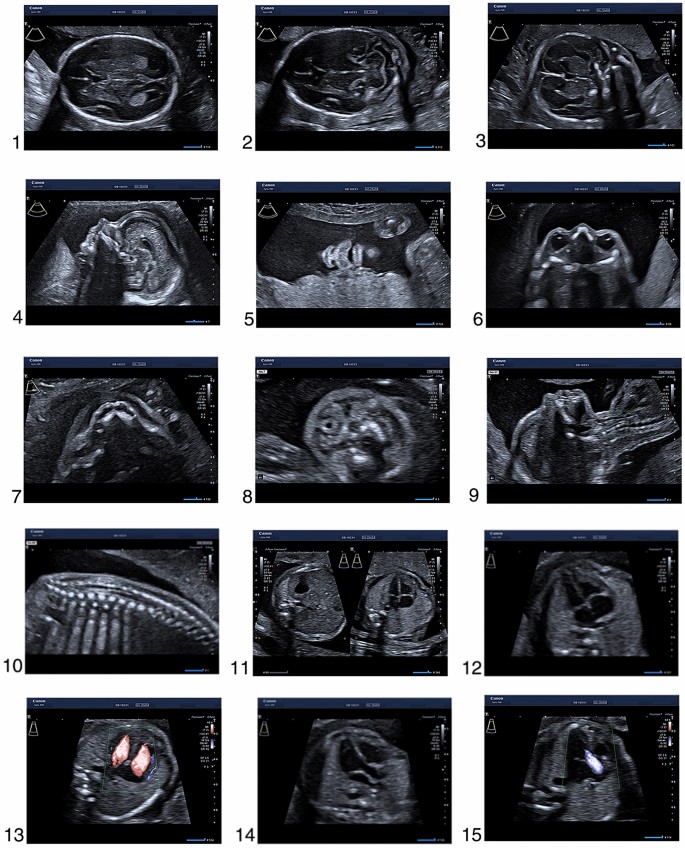

- 18-20 wks: Anomaly Scan (TIFFA).

⭐ TIFFA (18-20 wks) detects major fetal structural anomalies.

⭐ Anomaly scan (TIFFA) is ideally performed between 18-20 weeks gestation for detecting major structural fetal abnormalities.

> ⭐ The anomaly scan (Level II USG) around **18-20 weeks** is crucial for detecting major structural fetal abnormalities.

- Anomaly scan (TIFFA): crucial at 18-20 weeks for fetal structural defects.